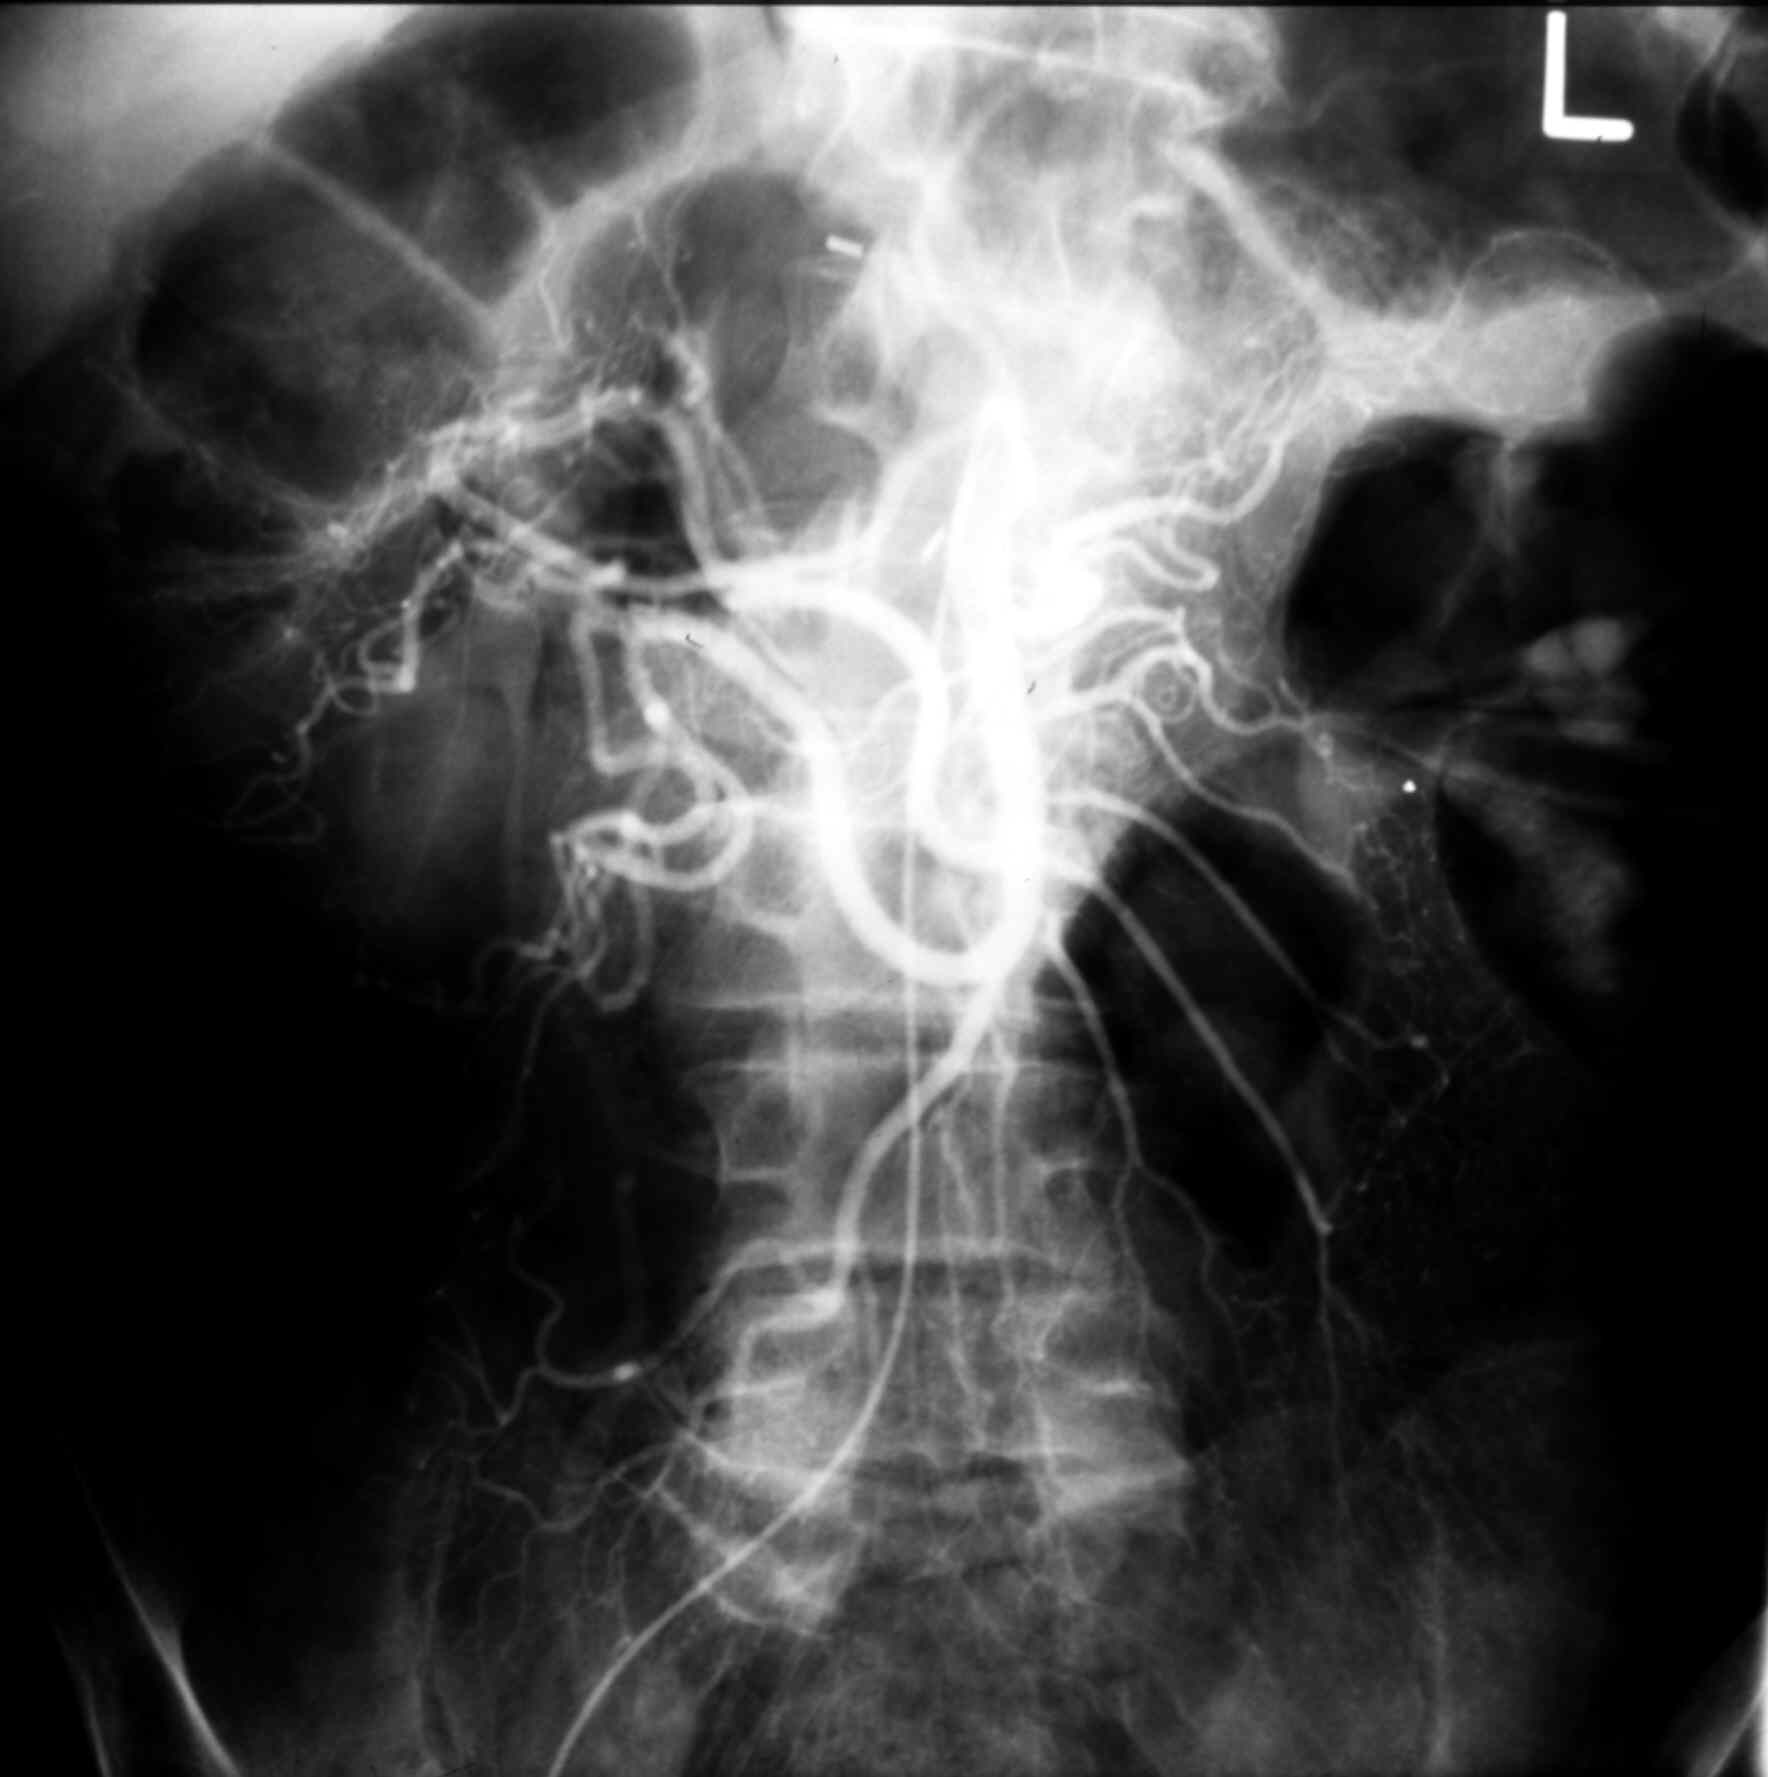

Radiology - MS I 119 Normal Superior Mesenteric Arteriogram - Arterial Phase

Identify: Superior Mesenteric A., Ileocolic A., Middle Colic AA., Jejunal Brs., Ileal Brs.